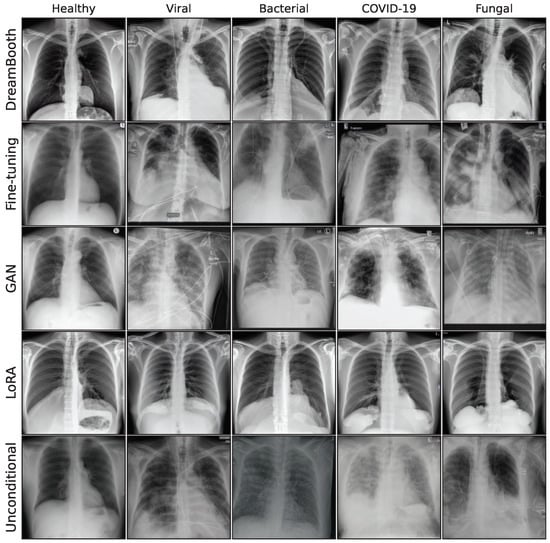

3.2. Image Synthesis

This subsection describes the generative models used in this work. We utilize a special GAN model, a Denoising Diffusion Probabilistic Model (DDPM), and 3 different fine-tuning approaches for a Stable Diffusion [34] model: standard fine-tuning, Low-Rank Adaption (LoRA), and DreamBooth. Our aim is to compare the performance of a GAN model to more recent diffusion-based architectures, building on the GAN proposed in Schaudt et al. [35]. Figure A2 in the Appendix A shows a collection of synthetic images for all generative models.

Figure A2. Sample synthetic images from all classes and methods.